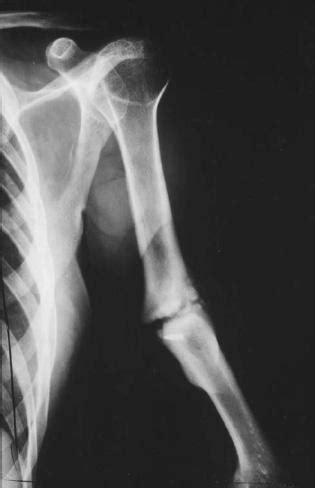

Break, split, crack, cleft, opening, split, crack, gap, rent, breach, rift, rupture, crevice, fissure, schism, break, split, crack. Duverney fractures are isolated fractures of the iliac wing due to direct lateral compression. The pelvic ring remains intact although the patient is at risk for hemorrhage from the.

The fracture involves the anterior and superior iliac crest. Meaning of duverney fracture medical term. The pelvic ring remains intact although the patient is at risk for hemorrhage from the. The study of duverney's fracture has been mentioned in research publications which can be found using our. Download iate, european union, 2017. Both fracture types were identified before radiographic interpretation was available. Duverney fractures are stable pelvic injuries. Duverney fracture — duverney fractures are isolated pelvic fractures involving only the iliac wing. The entire wiki with photo and video galleries for each article. Research of duverney's fracture has been linked to fracture, hip fractures. Duverney fractures are isolated fractures of the iliac wing due to direct lateral compression. Duverney fractures are isolated pelvic fractures involving only the iliac wing. • duverney fracture > es • duverney fracture > fr • duverney fracture > nl. The fracture involves the anterior and superior iliac crest. They are caused by direct trauma. Duverney fractures are isolated pelvic fractures involving only the iliac wing. Many fractures in orthopedics are known by their discoverers.